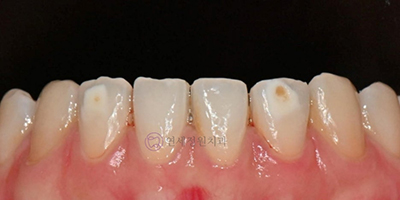

A recent patient visited our clinic with white spots on two lower front teeth that had been present since childhood and had recently turned brown. The brown discoloration was an advanced stage of the original white spots, requiring treatment. One tooth showed minor surface erosion along with the brown area. When brown spots are widespread, it’s often best to start with whitening to lessen their intensity, then perform ICON treatment about two weeks later.

In this case, since the brown spots were limited, we proceeded directly with ICON treatment. The procedure involved cleaning the teeth with fluoride-free polishing paste, etching the surface two to three times with 15% hydrochloric acid to create porosity, applying ICON resin, curing it, and then polishing for a smooth finish. Fortunately, the brown spots were minor and disappeared entirely after etching.

Brown Spots after Etching

Here’s a photo taken immediately after the ICON procedure. You can see significant improvement in both the white and brown spots without additional resin. While the teeth appear slightly dry in the photo, they look naturally aesthetic in a moist oral environment. Results will continue to improve over one to two weeks.